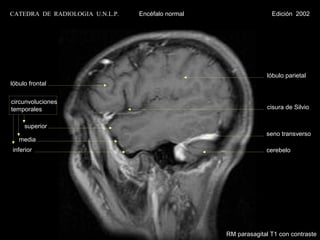

CATEDRA DE RADIOLOGIA U.N.L.P.   Encéfalo normal                  Edición 2002

lóbulo parietal

lóbulo frontal

circunvoluciónes

temporales                                                       cisura de Silvio

superior

seno transverso

media

inferior                                                        cerebelo

RM parasagital T1 con contraste